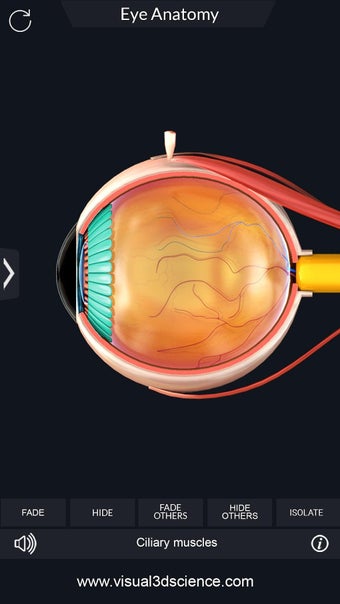

Изучите в деталях человеческий глаз и его анатомию с помощью этого простого в использовании бесплатного приложения для Android. Он позволяет масштабировать и вращать на 360° вокруг высокореалистичной 3D-модели глаза, а также рисовать на экране или прослушивать звуковое произношение каждого термина.

Вы можете выбрать X- просмотр луча, скрытие и отображение отдельных частей глаза, а также рисование или белый цвет на экране и обмен снимками экрана, звуковое произношение для всех анатомических терминов и многое другое.

Каждая часть разделена на отдельный вид, где вы можете можно увидеть название детали и ее расположение на глаз.